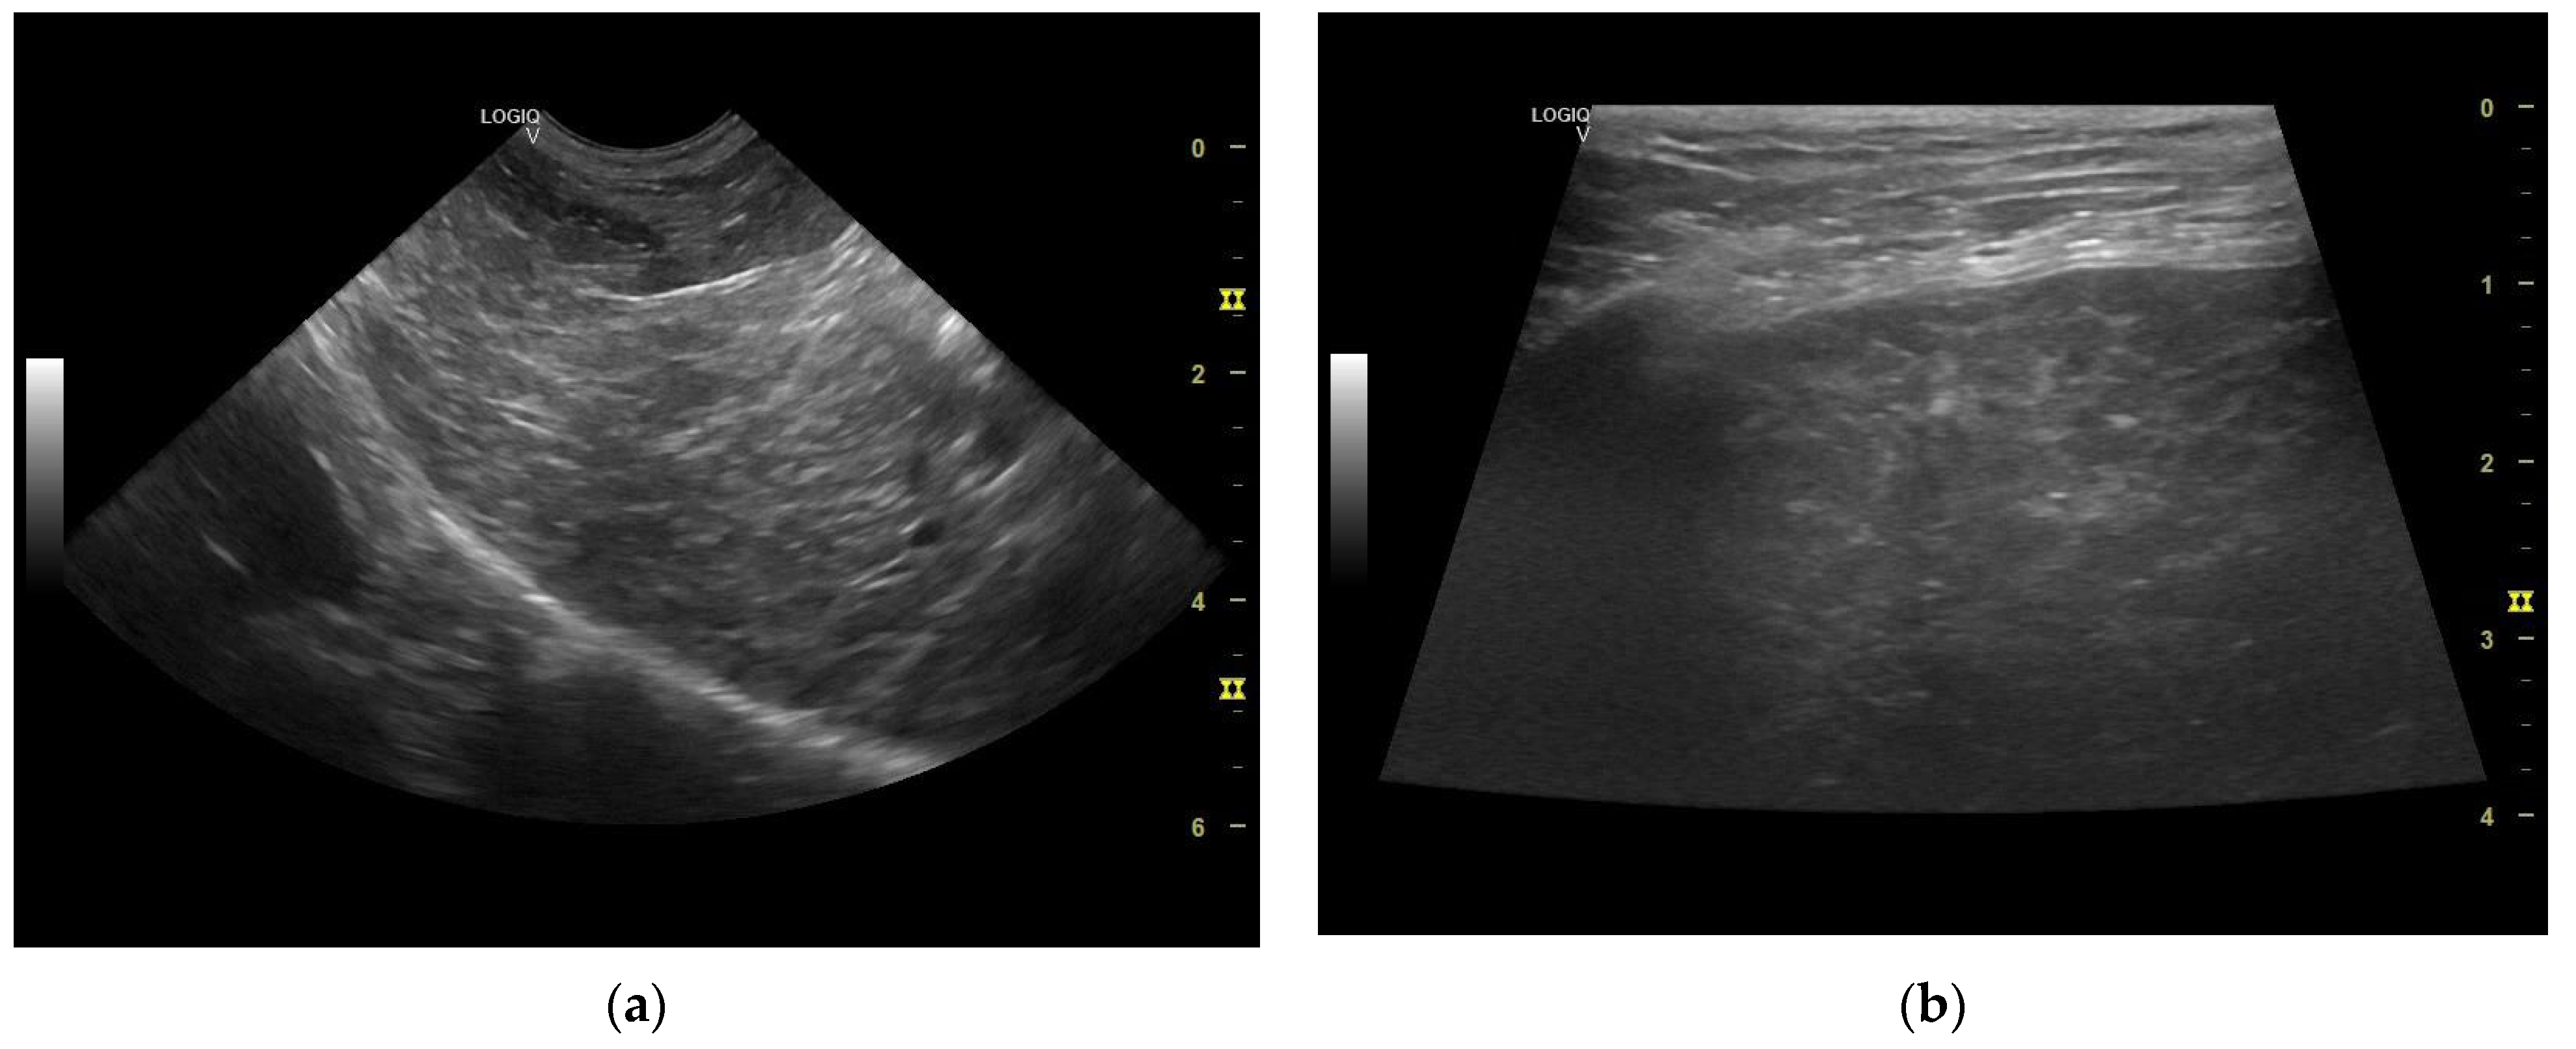

The liver appeared of normal size with non-homogeneous parenchyma, with multiple hyperechogenic strands diffusely dispersed throughout the parenchyma giving it a “Swiss cheese” appearance, with a slightly irregular outline and poorly distinguishable vascular walls (Figure 6 and Figure 7a,b). The gall bladder had a fine hyperechoic wall with anechoic content accompanied by hypoechoic, mobile, gravitationally dependent sediment in reduced quantity.

The ultrasonographical aspect of the liver as well as the normal size of the organ combined with the Swiss cheese-like appearance of the parenchyma corroborates the diagnosis of hepatocutaneous syndrome. Another differential diagnosis in absence of the dermatological findings could have been that of chronic hepatitis/liver cirrhosis, although the liver is reported to be reduced in size in these common conditions.

Figure 7. (a) Liver—non-homogeneous parenchyma (microconvex transducer). (b) Liver multiple hyperechogenic strands diffusely dispersed throughout the parenchyma—“Swiss cheese” appearance (linear transducer).